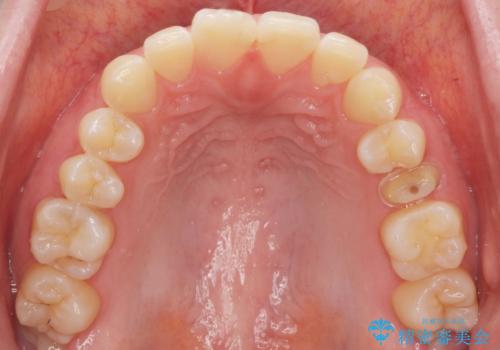

精査したところ、左上の小臼歯(左上5)は被せ物がないまま放置していたことにより、両隣の歯が寄ってきてスペースが少なくなり、また隣の歯(左上4)も虫歯になっていました。

隣の歯の虫歯治療(保険内のレジン充填)後、セラミッククラウンによる補綴を行いました。

以前つけた被せ物は1週間でとれてしまったそうで、歯ぎしりのご自覚もあることから、咬み合わせの調整を丁寧に行いました。

仮歯およびクラウンの仮付け期間を設け、はずれにくいことや咬み合わせに問題がないことを確認した上で本付けを行いました。

クラウンの種類:オールセラミッククラウン スタンダード